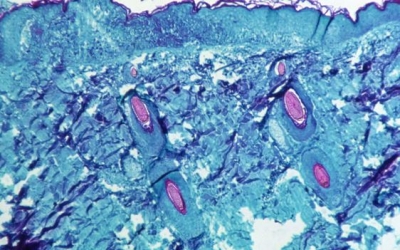

Ευλογιά των πιθήκων: Συναγερμός στην Ελλάδα μετά το δεύτερο κρούσμα - Γιατί υπάρχει ανησυχία - Οι αριθμοί παγκοσμίως 12/06/2022 - 09:43 - Κοινωνία

Μαγιορκίνης για ευλογιά πιθήκων: Σε πολύ συγκεκριμένους ανθρώπους τα εμβόλια – Πώς μεταδίδεται 25/05/2022 - 06:57 - Κοινωνία

Προειδοποιήσεις επιστημόνων: Εύκολα μπορούμε να φτάσουμε στα 10.000 κρούσματα ευλογιάς των πιθήκων 23/05/2022 - 06:55 - Κοινωνία